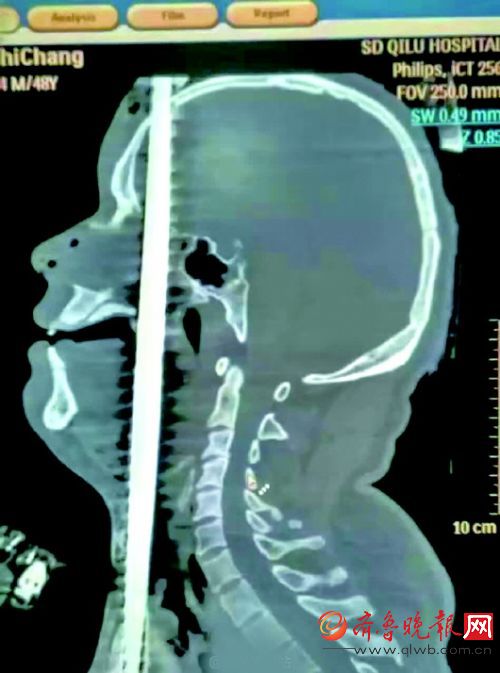

15 日, 朋友圈内被一则消息刷屏, “齐鲁医院成功救治一位贯通伤患者” 。 知情人士介绍, 该患者是一位 40 余岁的男性, 在高空作业时坠落, 被一根竖立在地面上的钢筋从阴部到头顶贯穿全身。 医院出动了神经外科、 口腔科、 耳鼻喉科、 胸外科、 心外科等多科室骨干人员参与救治, 消防队员也参与进来。 最终医护人员顺利将钢筋取出, 目前伤者生命体征稳定。

与此同时, 济南市公安消防支队历下大队泉城广场中队副中队长刘博威也接到报警电话。 五分钟后, 刘博威和七名队友赶到齐鲁医院急诊室。 “整个钢筋从伤者阴部贯穿到头顶,头顶上方有30厘米左右, 身体下侧也穿出二三十厘米。 ”

经检查发现, 该钢筋是从患者的阴部插入, 途经泌尿系统、 肝脾、 心脏和颈动脉, 然后从咽喉插入口腔、 鼻腔, 最后从头顶穿出。 不幸中的万幸是, 钢筋在伤者体内恰好避开了关键器官和大动脉。 伤者被送到医院的时候口腔和鼻腔有血液流出, 不过神志依然非常清醒, 手部也能活动, 并且可以和医护人员正常进行语言交流。